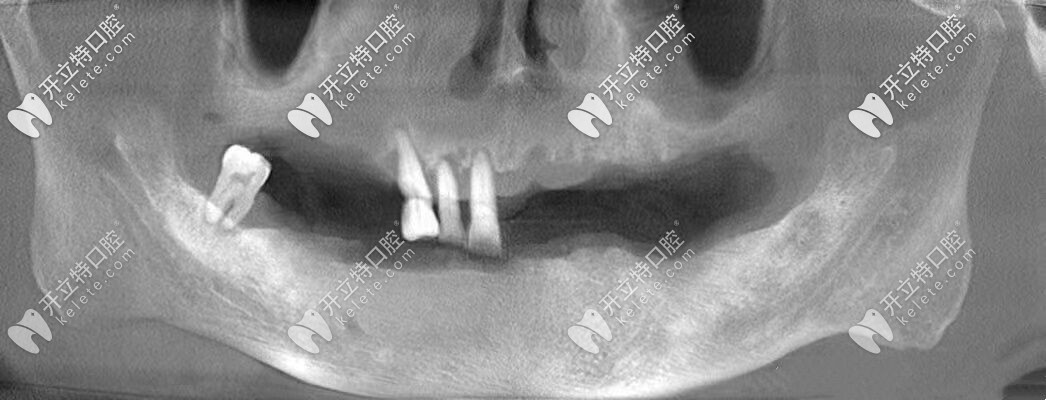

張叔牙齒的上頜僅剩3顆牙,下頜僅剩1顆牙,他之前一直戴的是活動(dòng)假牙,但是當(dāng)看著支持掛鉤的基牙一顆顆松動(dòng)、齲壞到拔除,張叔的心里也是很難過的。

由于常年戴活動(dòng)假牙,導(dǎo)致自身牙槽骨的條件較差,醫(yī)生給張叔設(shè)計(jì)了全口即刻種植牙的方案,沒想到3個(gè)小時(shí)左右的時(shí)間就完成了種植牙,并且真的是當(dāng)天種牙,當(dāng)天吃飯?。?/p>